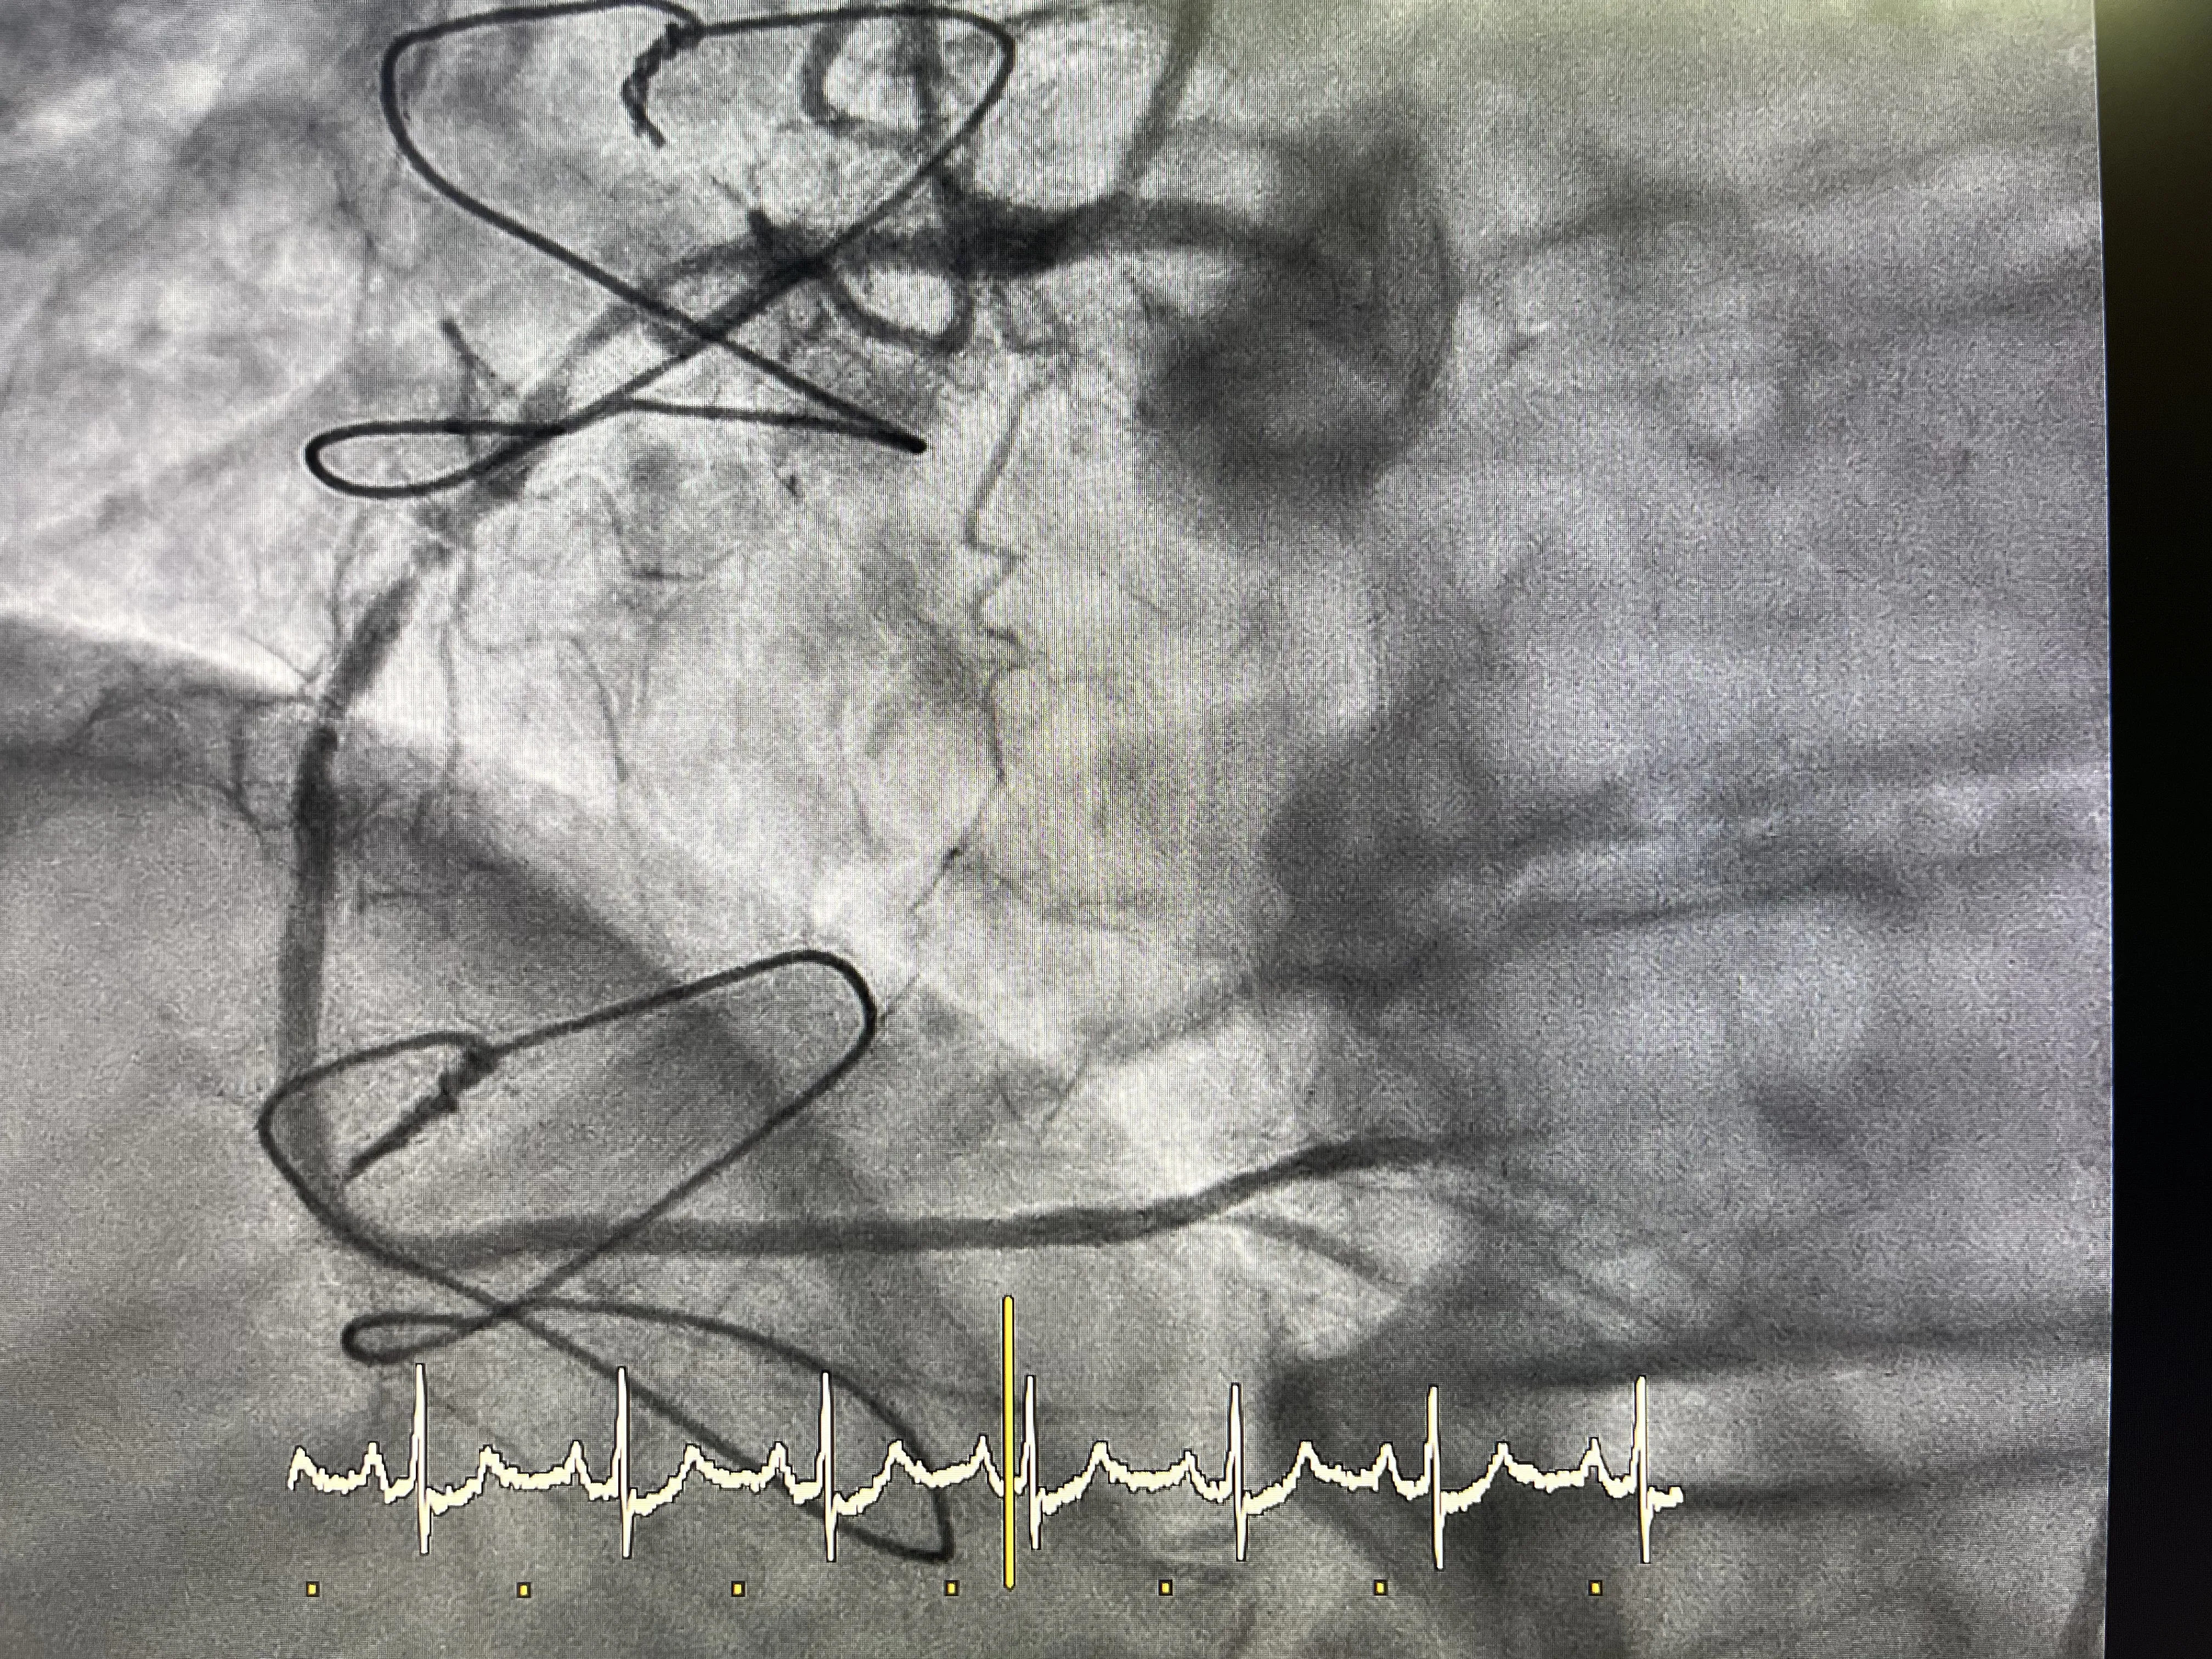

Hallazgos en la coronaria derecha: enfermedad extensa

Durante el cateterismo, se observó que la arteria coronaria derecha del paciente presentaba una enfermedad extensa. Esta condición implica que hay múltiples áreas de estrechamiento o bloqueo en la arteria, lo que puede limitar el flujo sanguíneo y contribuir a los síntomas de angina. La enfermedad extensa en la coronaria derecha es un desafío significativo, ya que puede requerir intervenciones adicionales para mejorar el flujo sanguíneo.

Hallazgos en la coronaria izquierda: circunfleja y descendente anterior

En cuanto a la coronaria izquierda, se identificó que el ostium de la arteria circunfleja estaba a punto de obstruirse completamente. Además, la arteria descendente anterior estaba ya completamente bloqueada. Sin embargo, gracias al bypass previamente realizado, la descendente anterior está siendo irrigada adecuadamente, lo que mitiga el impacto de la obstrucción en el flujo sanguíneo al corazón.